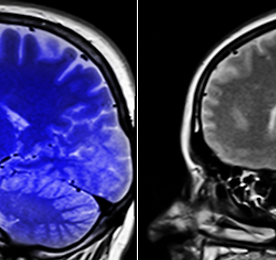

5월 두경부 MRI 건강보험 적용 시작 5월 두경부 MRI 건강보험 적용 시작 MRI(Magnetic Resonance Imaging, 자기공명영상)이라는 것은 자기장을 발생하는 큰 자석 통안에 인체가 들어가게 한 뒤 고주파를 쏘아 인체에서 메아리와 같은 신호가 발산되는것을 받아 디지털 정보로 변환하여 영상화 하는 것이다.뇌,뇌혈관 등 MRI 건강보험 적용 확대를 시작하여 오는 5월에는 두경부 눈, 귀, 코, 안면 등 MRI 검사가 건강보험 적용이 되어 환자의 부담이 3분의1 정도 수준으로 줄어들게 된다. 증증 질환이 의심이 되어도 MRI 검사 결과가 뇌종양, 뇌경색, 뇌전증, 혈관종, 악성종양 등 질환이 진단 된 환자만 건강보험 혜택을 받을 수 있었던 MRI 검사였지만, 의사가 MRI 검사를 통한 정밀 진단이 필요하다고 판단한 경우까지 건강.. 더보기